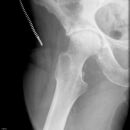

Schlecht festgeschraubt